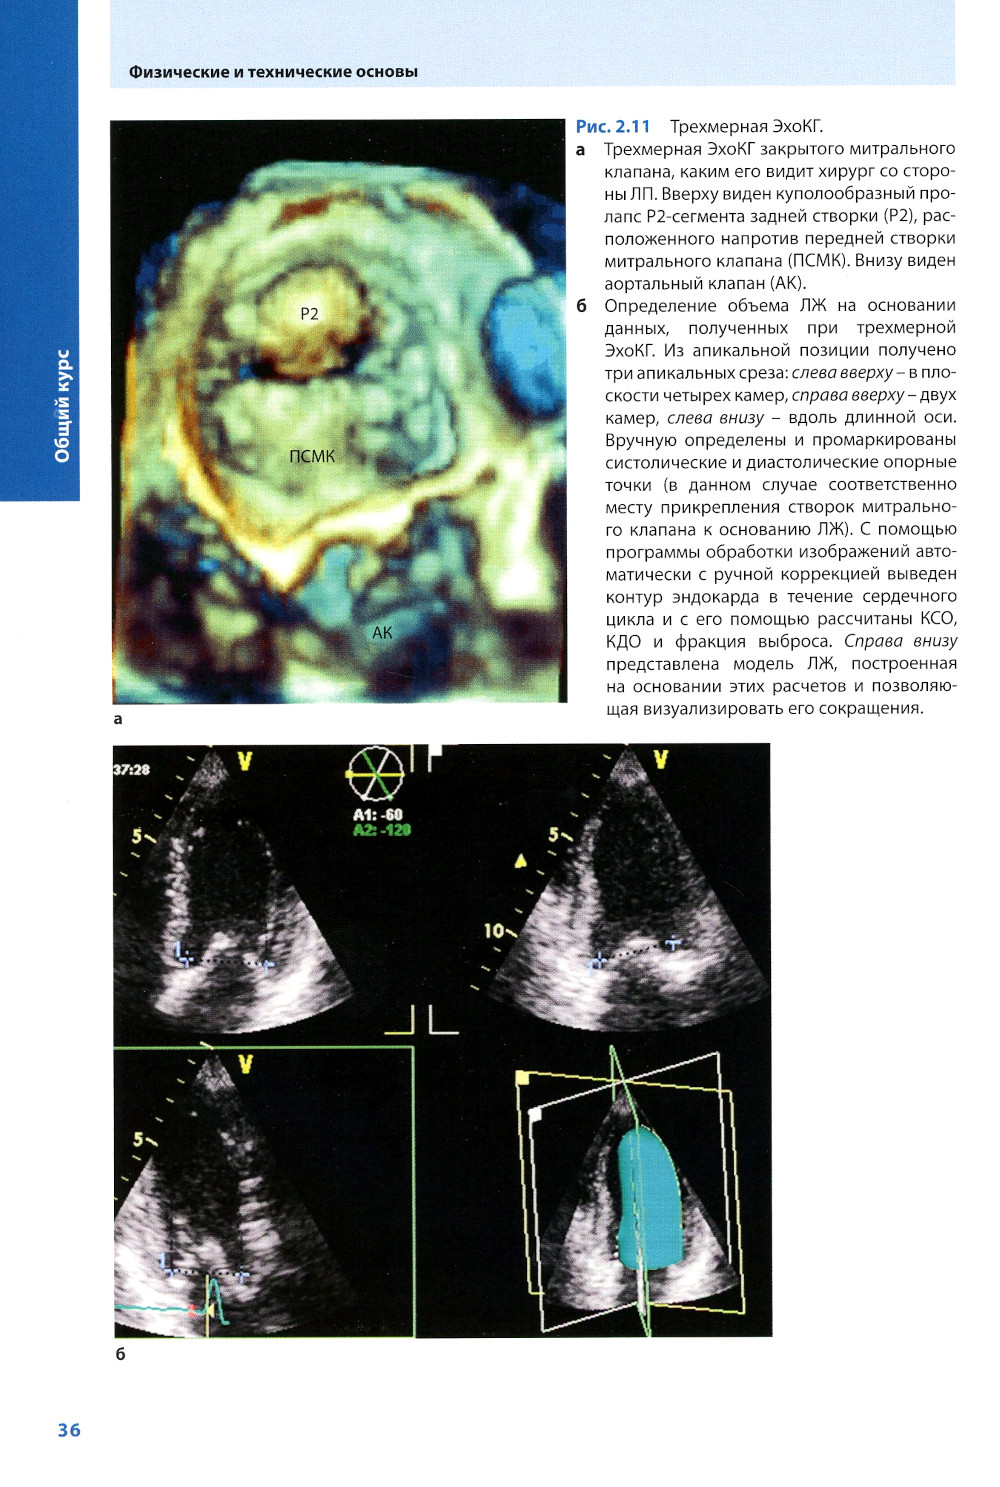

В книге рассмотрены физико-технические основы ЭхоКГ без излишней детализации, которая может затруднить усвоение клинического материала, методика проведения трансторакальной и чреспищеводной ЭхоКГ и ее основные режимы: М-режим, двух- и трехмерная ЭхоКГ, допплеровское исследование со всеми его вариантами, в частности непрерывно-волновой допплерографией, импульсно-волновой, тканевой допплерографией, цветовым и энергетическим допплеровским картированием. Разбираются клинические ситуации, часто допускаемые ошибки и причины неправильной интерпретации результатов. Описана эхокардиографическая диагностика типичных неотложных состояний, наблюдающихся в практике кардиолога и интерниста.